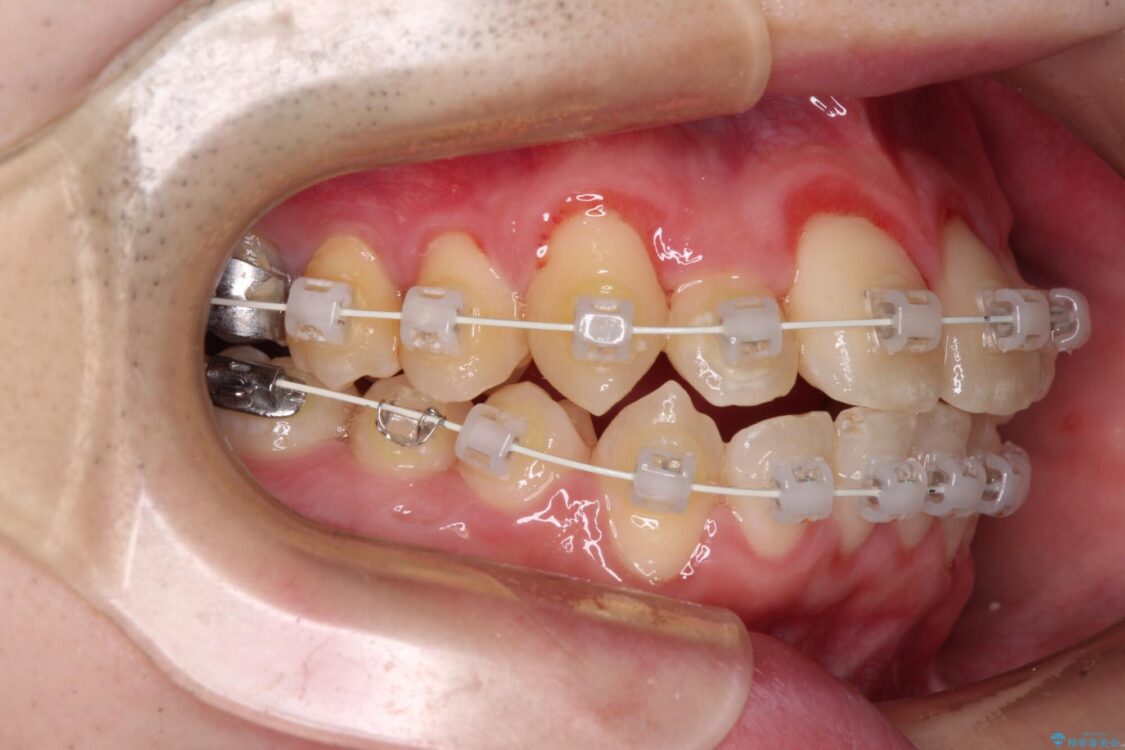

治療途中

• 全顎的なクロスバイト 補助装置を用いてワイヤー矯正 治療途中画像

シザーズバイト改善のために補助装置を使用しながら、ワイヤー装置にて全体の歯列を整えることとしました。

シザーズバイトは強く咬合する奥歯を移動させるため、多くの場合においてワイヤー矯正の装置のみでは改善が困難となります。

奥歯の咬み合わせ改善は治療初期からしっかりとアプローチする必要があるため、補助装置を積極的に利用します。